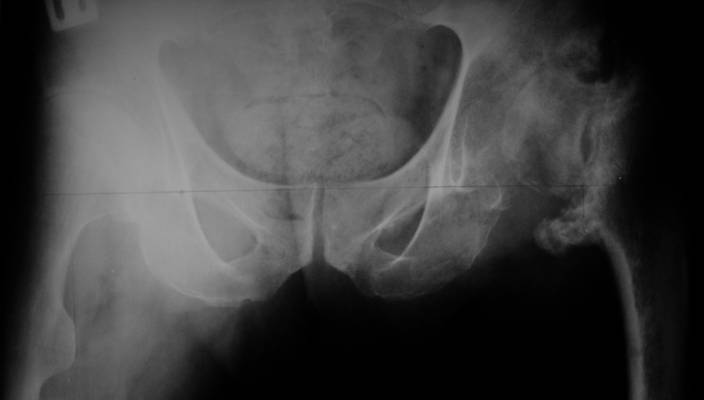

Еще пара фото, ситуация несколько иная, задачи те же, открытое вправление застарелого вывиха в 2002, молодой возраст. Сейчас госпитализирована для эндопротезирования.

А за счет чего такое укорочение? По снимку не видно соответствующего дефекта. Ну плюс приводящая контрактура - но все равно как-то уж больно много. Может, сделать снимки и таза обзорный с обоими проксимальными отделами бедра, и коенный суставов с приложенной линейкой какой?

Невозможно не согласиться с Анатолием, чтобы заниматься адекватным планированием как минимум прямая проекция таза должна быть сделана, как

максимум для оценки состояния мышц( насколько реально возможно низвести бедро) прямая проекция таза с тракцией за больную ногу.

I agree with Dr Eid's comments. The origin of the 8 cm leg length difference is a puzzle. Is this a clinical measurement? In that case contracture of the joint might affect the measurement. Can we see an AP pelvis to include both hip joints (including a calibration object with a known length) so that the difference in leg lengths that can be ascribed to the hip deformity and bony reabsorption can be measured. This sort of xray will help with templating for the TJR also. I would be very tempted to do a one stage procedure and accept some shortening. Shoe lifts should take care of a 3-4 cm difference.

До травмы проблем с ногой не было. Укорочения, болей и т.п. не отмечал. Сегодня перемерял укорочение - меньше 7 см намерять не

По уровню малых вертелов (с учетом рентгеновского увеличения) получается 5 см. Клинически ногу низвести путем тракции невозможно. Из движений - сгибание до 40*, остальные движения "символические".

Ортопедическое укорочение пострадавшей ноги может быть и 7, и 10 см. за счет контрактур в тазобедренном суставе, а вот истинное укорочение, судя по представленным рентгенограммам, вряд ли больше 4 см.